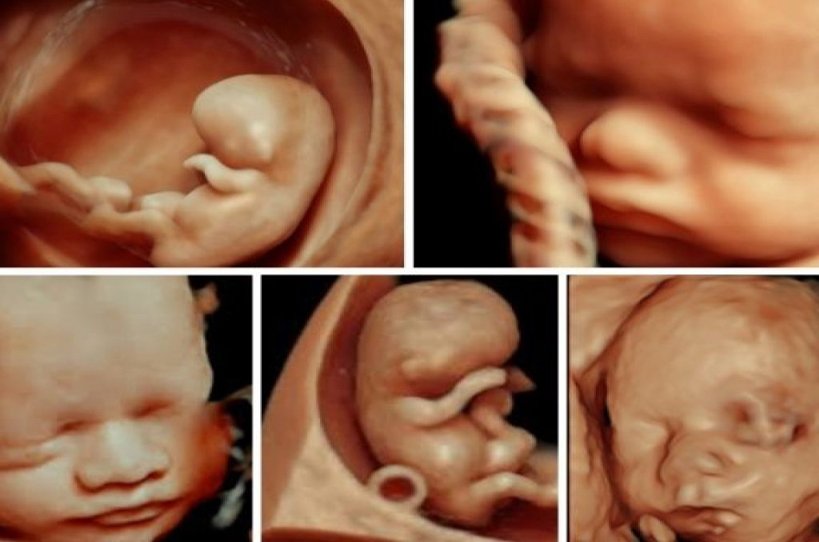

Ultrasound scans including 3D and 4D are more like a real-time photograph of your baby. With 3D scanning, many pictures of the child are taken in 2D and then merged to create a 3D image effect. With 4D scanning, pictures are made in real time and you can see what your child is doing in your womb at the time, such as moving of legs and arms or opening of the eyes.

In Advance Diagnostics, the best sonographer will help you with the complete procedure. A probe or a transducer coated with a conductive gel is a device used to perform the ultrasound, which sends a signal inside the womb. 3D ultrasounds create a three-dimensional image, while 4D ultrasounds create a live video effect – you can watch the movement of hands and legs, smiles, and even the yawns of the foetus. Both the scans are safe and painless.